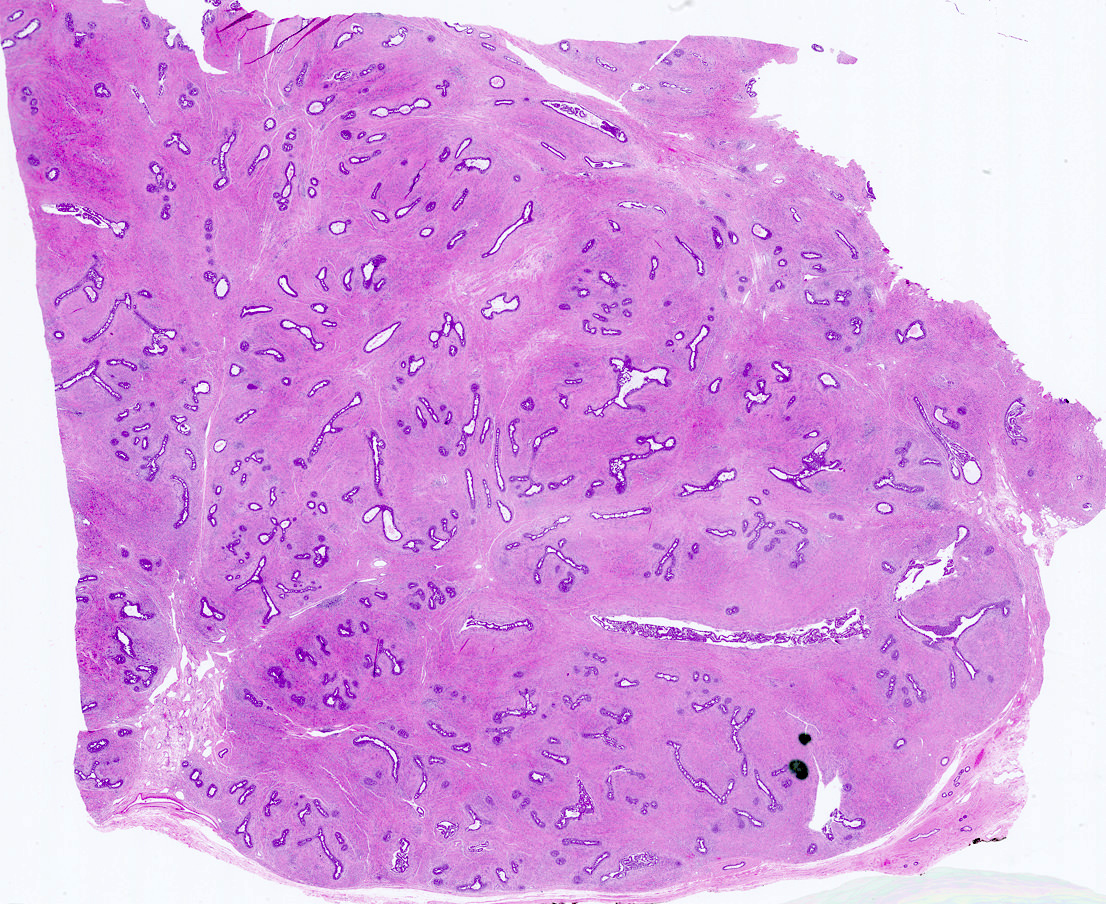

Microscopic (histologic) description

- Well circumscribed, unencapsulated

- Biphasic tumor, proliferation of both glandular and stromal elements

- Glandular component

- 2 recognized growth patterns (of no clinical significance, both patterns may occur within a single lesion)

- Intracanalicular: glands are compressed into linear branching structures by proliferating stroma

- Pericanalicular: glands retain open lumens but are separated by expanded stroma

- Glandular elements have intact myoepithelial cell layer

- Stromal component

- Generally uniform cellularity within a given lesion

- Collagen and bland spindle shaped stromal cells with ovoid or elongated nuclei

Microscopic (histologic) images

Contributed by Gary Tozbikian, M.D., Debra Zynger, M.D., Azadeh Khayyat, M.D. and Julie M. Jorns, M.D. (Case #533)